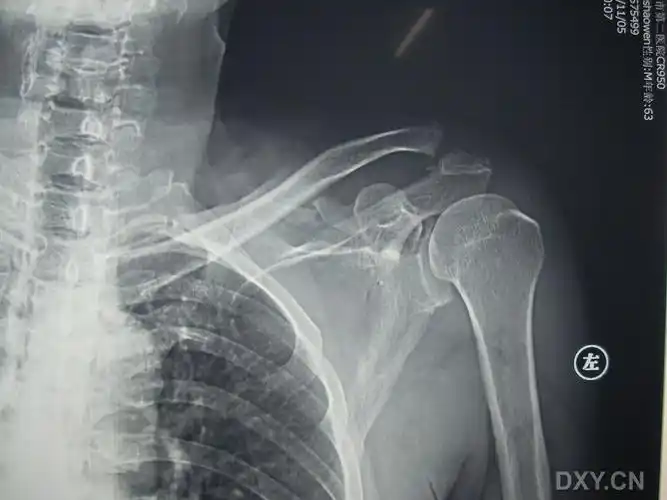

求助:这例肩锁关节脱位合并喙突骨折怎么手术入路?